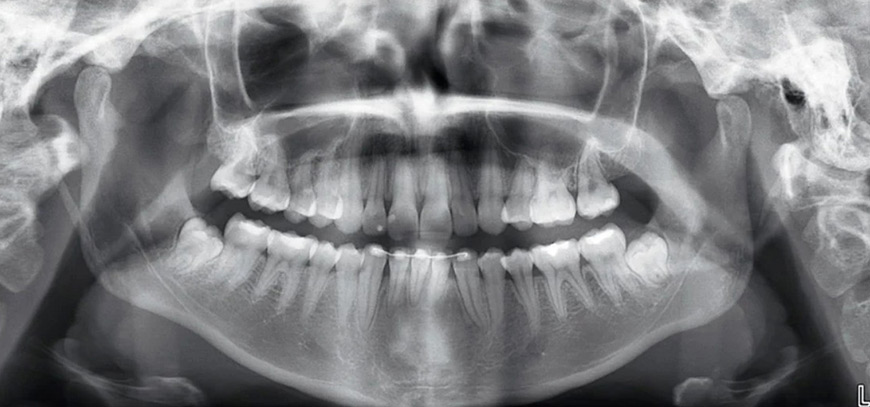

Dünyanın en kompakt Panoramik röntgen cihazı ile mükemmel görüntüler elde ederek, Ödüllü tasarımı ile hem hızlı, hem yorulmadan beklemeden tam otomatik kullanım sağlayarak hastalarımıza üstün kalite ile hizmet vermekteyiz. Doğru anatomik konumlandırma noktalarını gösteren üçlü lazer ışını sistemimizin desteklediği pozisyonlama ile, hastalarımızı önden ve yandan takip edebilmekteyiz. Ayrıca cihazımızın radyasyon oranı diğer cihazlara oranla çok düşüktür ve zararsızdır. Çocuk modu mevcuttur ve ona görede radyasyon oranı hiç yok denecek kadar azdır.